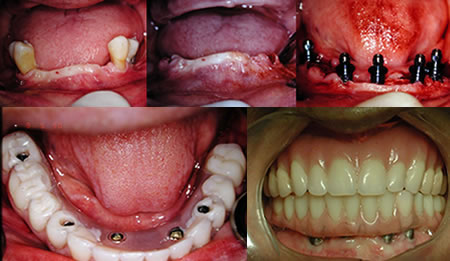

Carga Imediata

Para muitos pacientes, a necessidade de estar sem a prótese durante um período de tempo, após a instalação dos implantes, pode ser considerada inconveniência em função do convívio social e atividades profissionais. O termo carga imediata pode ser definido como instalação de implantes osseointegrados em condições ideais à estabilidade primária, seguida de ativação protética ( colocação dos dentes ) 48 horas após a cirurgia. Esta definição era aplicada à instalação de múltiplos implantes dentários e a contenção entre os mesmos promovendo um efeito de estabilidade. Com estudos recentes podemos colocar o implante unitário e colocar o dente no mesmo instante, sendo observado somente uma boa estrutura óssea.

Quanto tempo leva para ser feito ?

O processo leva cerca de 2 ou 3 dias variando de acordo com o número de dentes a serem implantados no paciente. Em reabilitações totais, na média, são realizados 6 a 8 implantes para cada arcada ( superior ou inferior ) em uma única sessão cirúrgica. Com o modelo em mãos é confeccionada a infra-estrutura que é provada em uma sessão, normalmente no dia seguinte a cirurgia. A infra-estrutura volta ao laboratório onde recebe os dentes. Depois a peça pronta é colocada.

Podemos prever o resultado ?

Observando o estudo comparativo entre a técnica convencional estabelecida por BRANEMARK e o protocolo de carga imediata temos como grandes vantagens a diminuição do tempo das consultas e a rapidez dos resultados oferecidos ao paciente, com efeito psicológico e social melhorados, já que os resultados geram bem estar funcional e estético. Os pacientes devem ser selecionados e a indicação estabelecida após controle sistêmico da saúde e das condições locais favorecidas para essa técnica. Comparada com a técnica convencional onde o paciente esperaria normalmente de 3 a 6 meses para a colocação dos dentes, a técnica da carga imediata pode ser uma ótima opção.